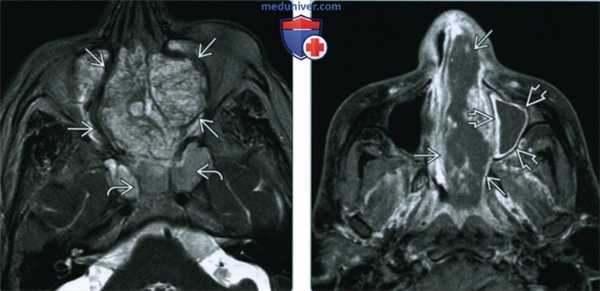

(Слева) При аксиальной КТ с КУ визуализируется большая аденокарцинома, неравномерно накапливающая контраст, и заполняющая верхние отделы полости носа и решетчатые пазухи. Опухоль прорастает кпереди в мягкие ткани спинки носа и разрушает глазничную пластинку с обеих сторон.

(Справа) При сагиттальной МРТ Т1 ВИ визуализируется крупная аденокарцинома, заполняющая полость носа и распространяющаяся в носоглотку. Опухоль не прорастает через основание черепа, но распространяется в подкожную клетчатку спинки носа.

(Слева) При аксиальной МРТ Т2 ВИ FS: определяется большая гиперинтенсивная неоднородная аденокарцинома решетчатых пазух, заполняющая полость носа с объемным воздействием на обе орбиты. В сфеноидальных пазухах виден «запертый» секрет.

(Справа) При аксиальной МРТ Т1 ВИ С+ FS в полости носа слева определяется аденокарцинома, неравномерно накапливающая контраст. Обратите внимание на обструкцию левой верхнечелюстной пазухи с периферическим (не центральным) контрастированием секрета.